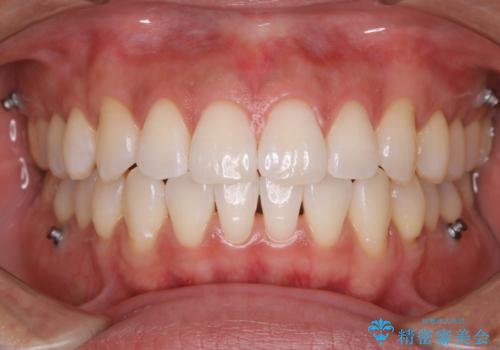

インビザラインの矯正中のクリーニング